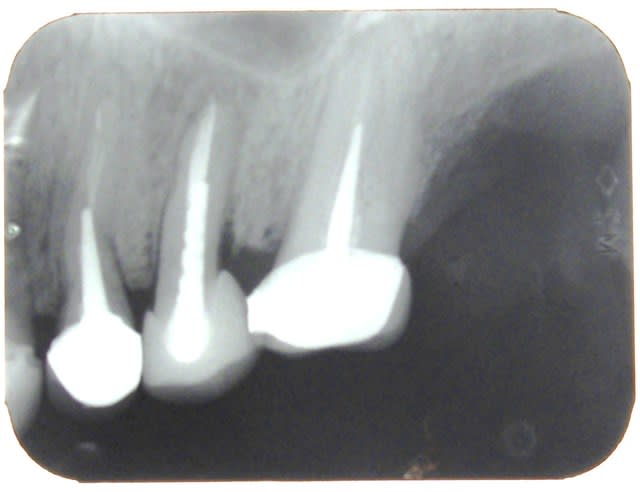

radio de controle du cas de la pm .

au niveau de l'apex ca va

parcontre au niveau de la racine , l'image n'est pas tres jolie . une chose de sure , cela ne ressemble pas a un ligament .

bon le cliché n"est pas net non plus , ceci expliquant aussi cet aspect flou

pas de mobilité

belle gencive

bref d'un point de vue clinique RAS.